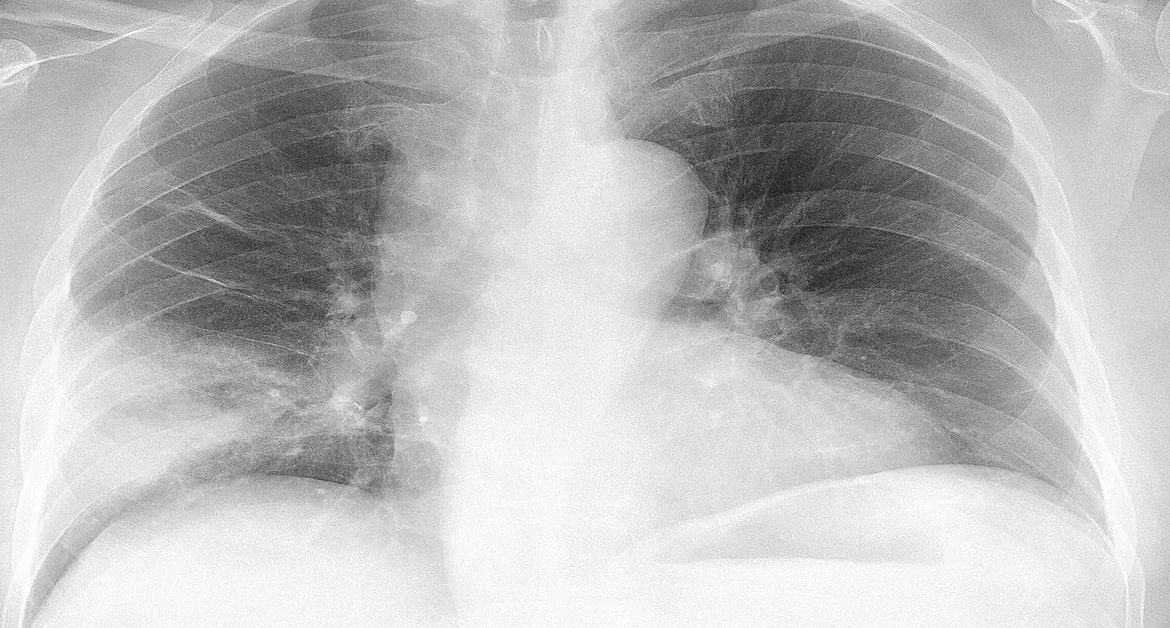

Tanı genellikle klinik muayene ve akciğer grafisi ile konur. Şüpheli durumlarda kan testleri ve ileri görüntüleme yöntemleri kullanılır. Özellikle risk grubundaki hastalarda aspirasiyon pnömonisi hızlı ilerleyebilir. Bu nedenle erken müdahale hayati önem taşır.

Tanı için doktor muayenesi ve akciğer grafisi kullanılır. Şüpheli durumlarda kan testleri veya ileri görüntüleme yöntemleri eklenebilir. Erken teşhis, tedavi başarısını artırır. Risk grubundaki kişiler yakından izlenmeli ve önleyici tedbirler almalıdır. Bu, komplikasyonları azaltır.